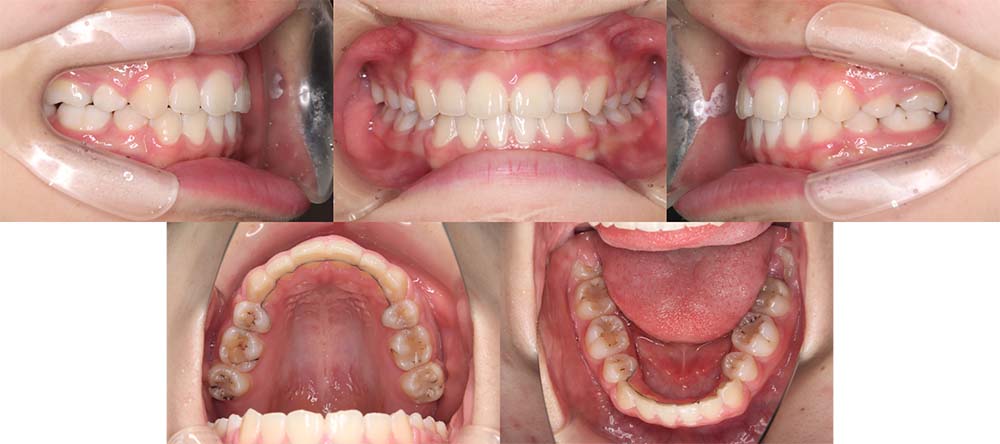

| 症例分類 | 叢生、上顎前突、口唇突出 |

| 診断名 | 下顎重度叢生を伴う骨格性上顎前突 |

| 主訴 | 歯並びが悪い、ものがよく噛めない、口元が気になる、歯科医師に勧められた |

| 年齢 | 22歳10ヶ月 |

| 性別 | 女性 |

| 抜歯部位 | 上下左右の第一小臼歯(4本) |

| 使用装置 | 表側のワイヤー装置 |

| 治療期間 | 2年2ヶ月 |

| 保定装置 | 固定式保定装置、取り外し式保定装置(8時間) |

| 費用 |

[検査・診断料] ¥49,500 [基本施術料] ¥792,000 [調整料] ¥4,400/回 [抜歯] ¥5,500/本 [保定装置] ¥55,000(税込) 抜歯や虫歯治療は他院にて費用が別途かかります。(抜歯¥4,000〜10,000/本)

下顎前歯重度叢生と上顎歯列の前方位、口唇閉鎖不全、口唇突出感があるため、上顎両側第一小臼歯と下顎両側第一小臼歯を抜去して治療を行いました。上顎前歯をしっかりと舌側移動しないといけなかったため矯正用アンカースクリューを使用しました。

前歯がしっかりと舌側移動できたため、口唇閉鎖不全が改善され口唇突出感もなくなり、問題なく咬合させることができました。